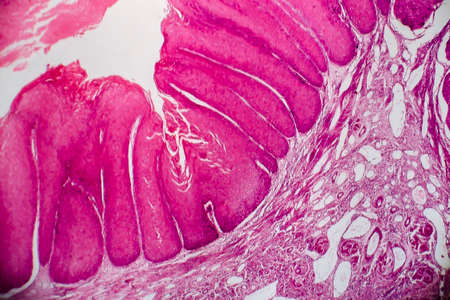

Bowen's Disease Tumor under the microscope 100x

Bowen's Disease Tumor under the microscope 100x